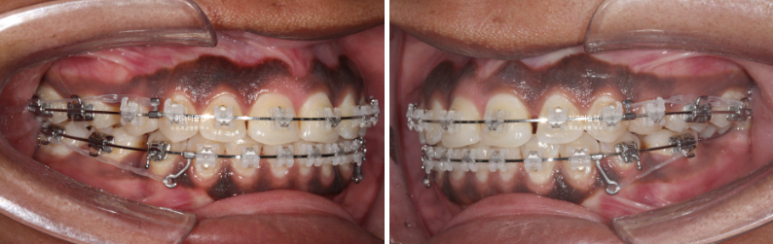

This is the patient’s condition at 1 year and 2 months after the start of treatment.

Approximately one-third of the extraction space remains.

At 2 years into treatment, closure of the extraction spaces was completed.

At this stage, the implant fixture was first placed in the mandibular posterior region, followed by intrusion of the supra-erupted opposing tooth.

For effective intrusion, a temporary orthodontic mini-screw was placed in the palate.